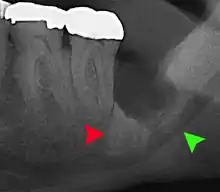

Impacted wisdom teeth are classified by their direction of impaction, their depth compared to the biting surface of adjacent teeth and the amount of the tooth's crown that extends through gum tissue or bone. Impacted wisdom teeth can also be classified by the presence or absence of symptoms and disease. Screening for the presence of wisdom teeth often begins in late adolescence when a partially developed tooth may become impacted. Screening commonly includes a clinical examination as well as x-rays such as panoramic radiographs.

If the tooth cannot be assessed with clinical exam alone, the diagnosis is made using either a panoramic radiograph or cone-beam CT. Where unerupted wisdom teeth still have eruption potential several predictors are used to determine the chance of the teeth becoming impacted. The ratio of space between the tooth crown length and the amount of space available, the angle of the teeth compared to the other teeth are the two most commonly used predictors, with the space ratio being the most accurate. Despite the capacity for movement into early adulthood, the likelihood that the tooth will become impacted can be predicted when the ratio of space available to the length of the crown of the tooth is under 1.[5]: 141